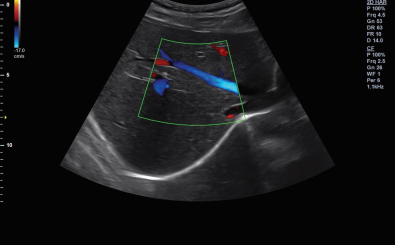

CLINICAL IMAGES

臨床影像

Abdomen

Directional Power Doppler Imaging